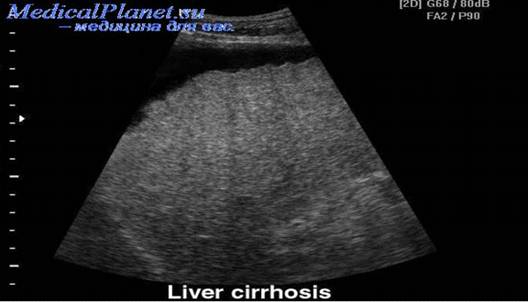

• УЗИ печени

Позволяет обнаружить изменение размеров печени и селезёнки, выявить акустическую неоднородность печёночной паренхимы и признаки портальной гипертензии.

Рис. 5. Цирроз печени на УЗИ